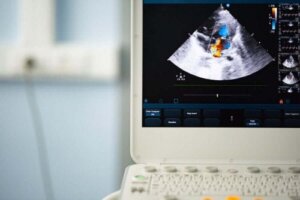

At lytte til hjertelyde med et stetoskop og et ekkokardiogram er to effektive teknikker til at diagnosticere denne tilstand.

Under undersøgelsen bruger de måske et stetoskop for at kunne høre uregelmæssig hjertebanken og også for tegn på mislyd. Derefter vil de for at bekræfte, at du har en bicuspid aortaklap, lave et ekkokardiogram, som hjælper med at vurdere, hvordan hjertet fungerer.